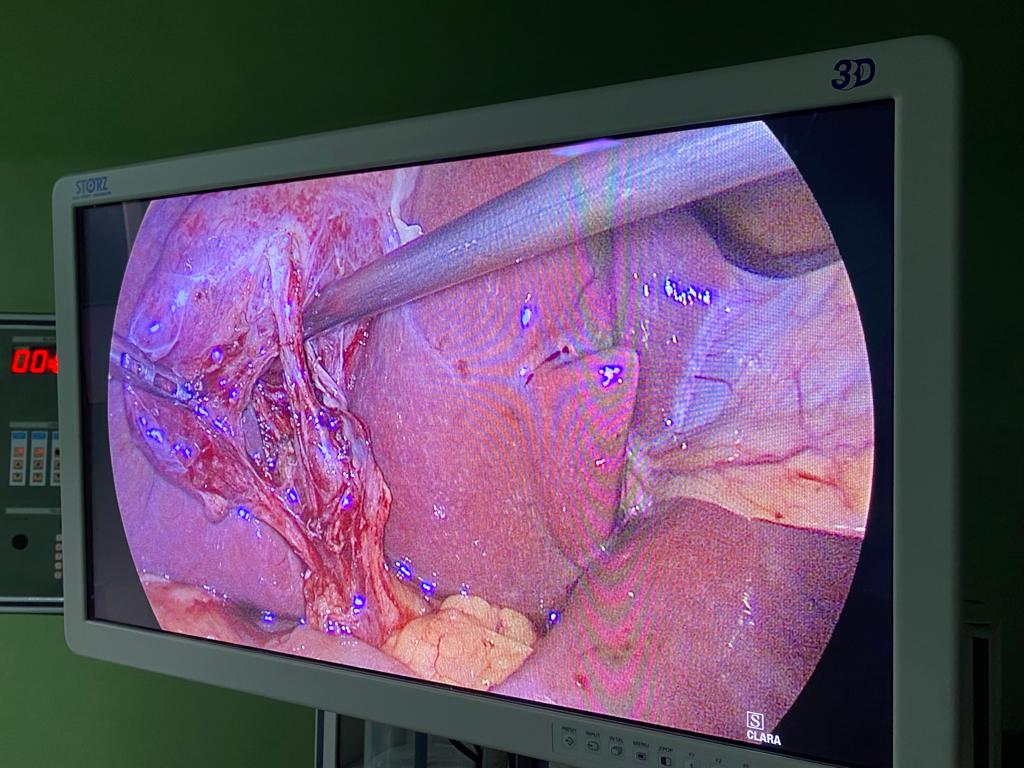

Difficult case of gallbladder done completely by Laparoscopically.

Acute Cholecystis, Mucocele Gallbladder with big stone at the neck. Completely done Laparoscopically